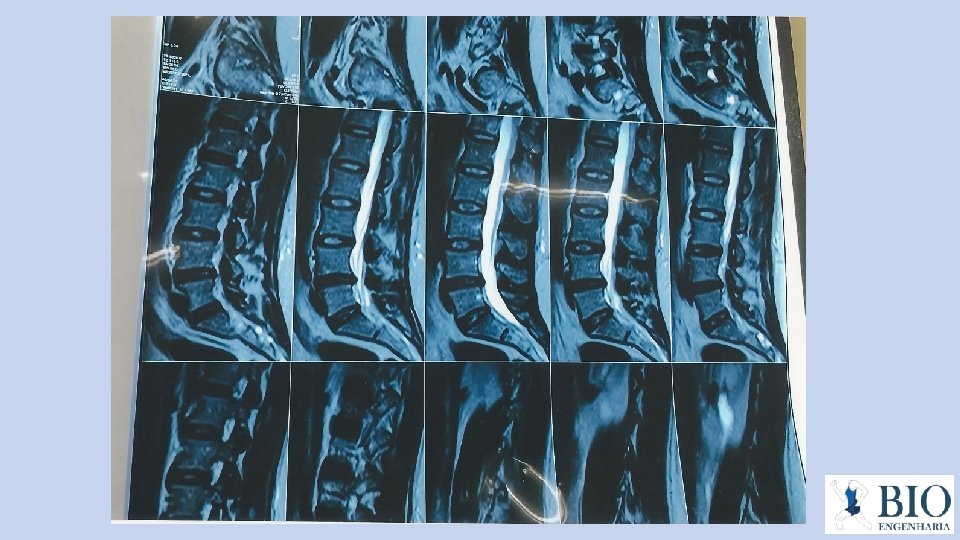

INDICAÇÃO: O Kit Cânula Nucleotomor Pulsante é um produto desenvolvido para efetuar uma descompressão de hérnias discais toraco-lombares por nucleotomia ou discectomia percutânea. É indicado na grande maioria dos pacientes com problemas de hérnias de discopatias degenerativas. Exemplos: • Hérnias discais contidas, • Hérnias foraminais sintomática e ciática, • Hérnias HIZ (higt intensity zone) disco preto zona de alta intensidade. O processo será realizado na região tóraco-lombar da coluna vertebral. É um procedimento minimamente invasivo, ou seja, com o mínimo de agressão ao organismo.

2 - com o auxílio do intensificador de imagens, localize o local exato para incisão da anestesia e da agulha.

Na imagem perfil é indispensável que se faça aferição no ap, pois essa agulha deve estar entre a linha média interna do pedículo correspondente e a apófise espinhosa da mesma vértebra. Atenção: a agulha não pode ficar antes nem depois, sob pena de ter riscos de danos cirúrgicos quer sejam vasculares ou radiculares.